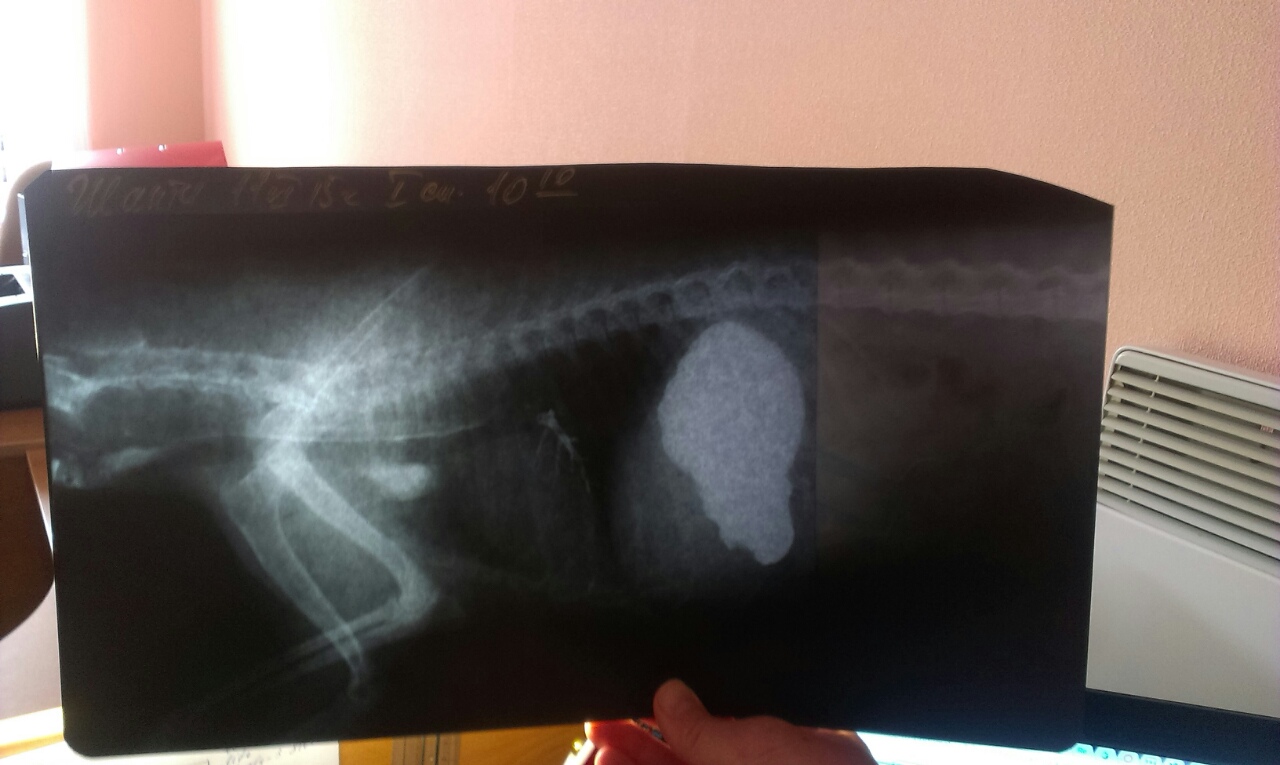

если такое качество снимков ОК - то сделаю оставшиеся. Это первый снимок после приема бария. Вот по шее и видно то, что вет посчитал дивертикулом

тут ссылка на рентген. Самый первый снимок с барием (в разных вариациях), где видно нечто на шее

Мои рентгенологи сказали, что не совсем корректно выполнено исследование. Нет бария в пищеводе, только по слизистой смазка. На шее немного видно, но это может быть связано с анатомией собаки. Скорее всего не успели снимки сделать, когда барий в виде кома идет по пищеводу. Про размеры сказать по одной проекции сказать сложно.

Там выложены все снимки - сразу после бария, через час и через восемь часов

Юля, они практически одинаковые. Врач подумал сначала, что это один и тот же снимок. Потом стали играть в игру " найди отличия". Доктор еще помнит, как нужно снимать на пленку простым, а не цифровым рентгеном.

Юль, в пищеводе бария нет. И затеков не видно. Но по тонкому слою смазки расширения не видно, пищевод ровненький.

я тоже не вижу ничего в пищеводе. Но мне кажется что все же проходимость частичная

из желудка выходит тоненький ручеек.... сколько здесь прошло времени с дачи бария?

и здесь интересный перешеек....

форма желудка чуть неправильная - 11Юлга писал(а):Ирина, а так по ссылкам открывается общая ссылка на все снимки

здесь желудок полностью с барием и стенки ровные, выходит он хорошо, но тонкой струйкой -16, сколько здесь прошло от приема бария?

и перешеек - 19. но здесь скорее всего каловые массы уже влияют....

Ира, ты про снимок на котором написано 18.40 стоя? Это перешеек в кишечнике, непроходимость? Первые снимки утром сделаны.

перешеек? да на этом снимке. Он настораживает.... но это вроде уже толстый кишечник, а я по клинике ищу проблему на выходе из желудка и в 12-ти перстной.энн писал(а):Ира, ты про снимок на котором написано 18.40 стоя? Это перешеек в кишечнике, непроходимость? Первые снимки утром сделаны.

Желудок только в боковой, а в прямой нет? Может это наслоение? По клинике высоко должно быть, но перешеек в Толстой кишке. Его быть не должно.

Ира, посмотри, что это за белое пятнышко в грудной полости. Если по костям ориентироваться то в углу, где ноги к лопатке крепиться. Мой рентгенолог предположил, что возможно это дивертикул. Но он не уверен, так как плохо знает анатомию собаки и собака лежит на боку, а у нас такой рентген делают стоя.